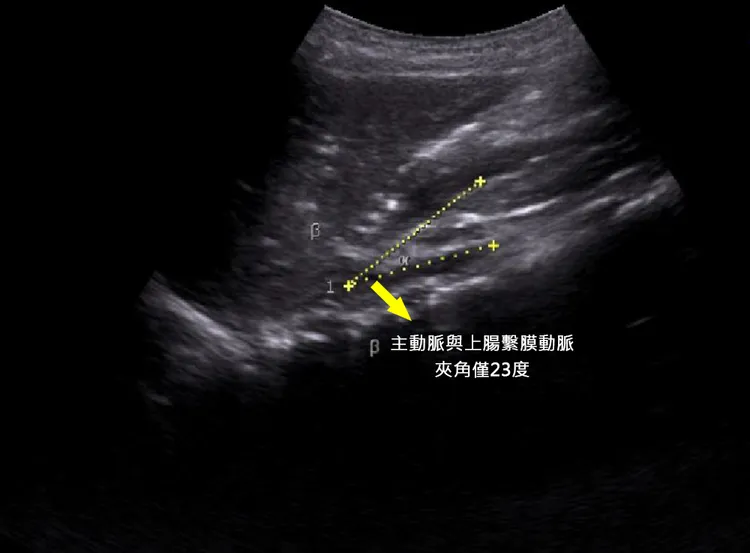

廖子涵醫師表示,經超音波和電腦斷層檢查,發現該男孩的主動脈與上腸繫膜動脈之間夾角只有23度,正常約38到65度之間,夾角過小原因常見為體重過輕,上腸繫膜動脈缺少脂肪支撐,壓迫到十二指腸,胃裡消化的食物較難順暢下到十二指腸,而導致食慾不振與頻繁的噁心嘔吐。

男童主動脈與上腸繫膜動脈夾角僅23度。院方提供